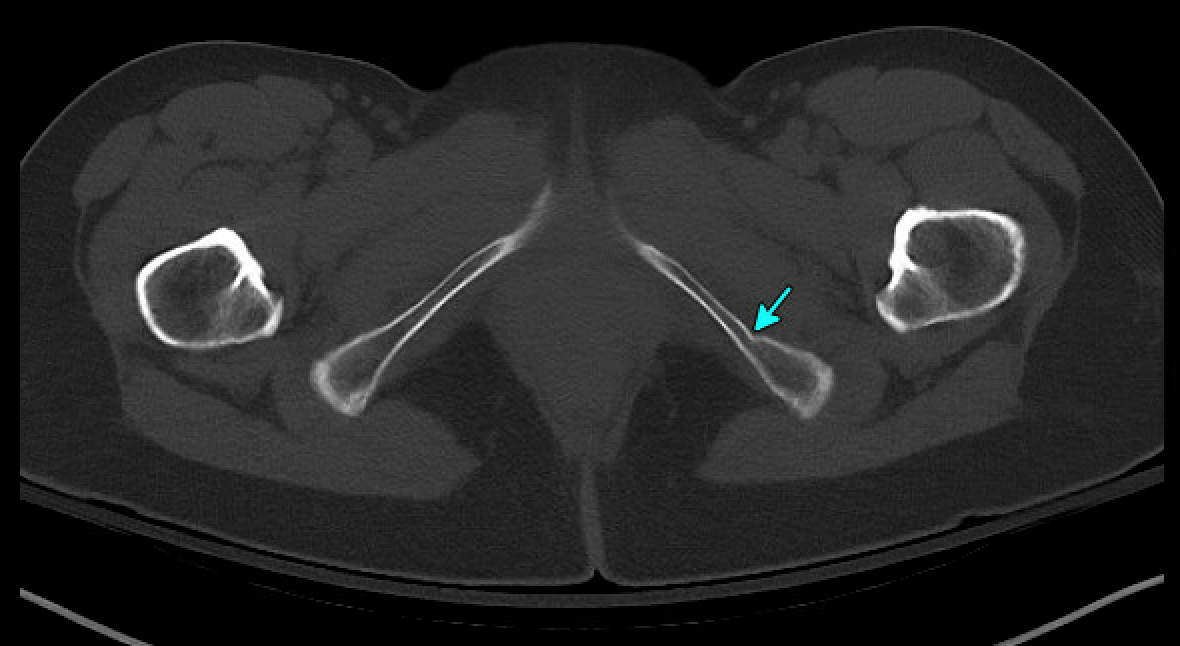

CT later confirmed fractures involving the left acetabulum and ilium, and bilateral pubic rami.